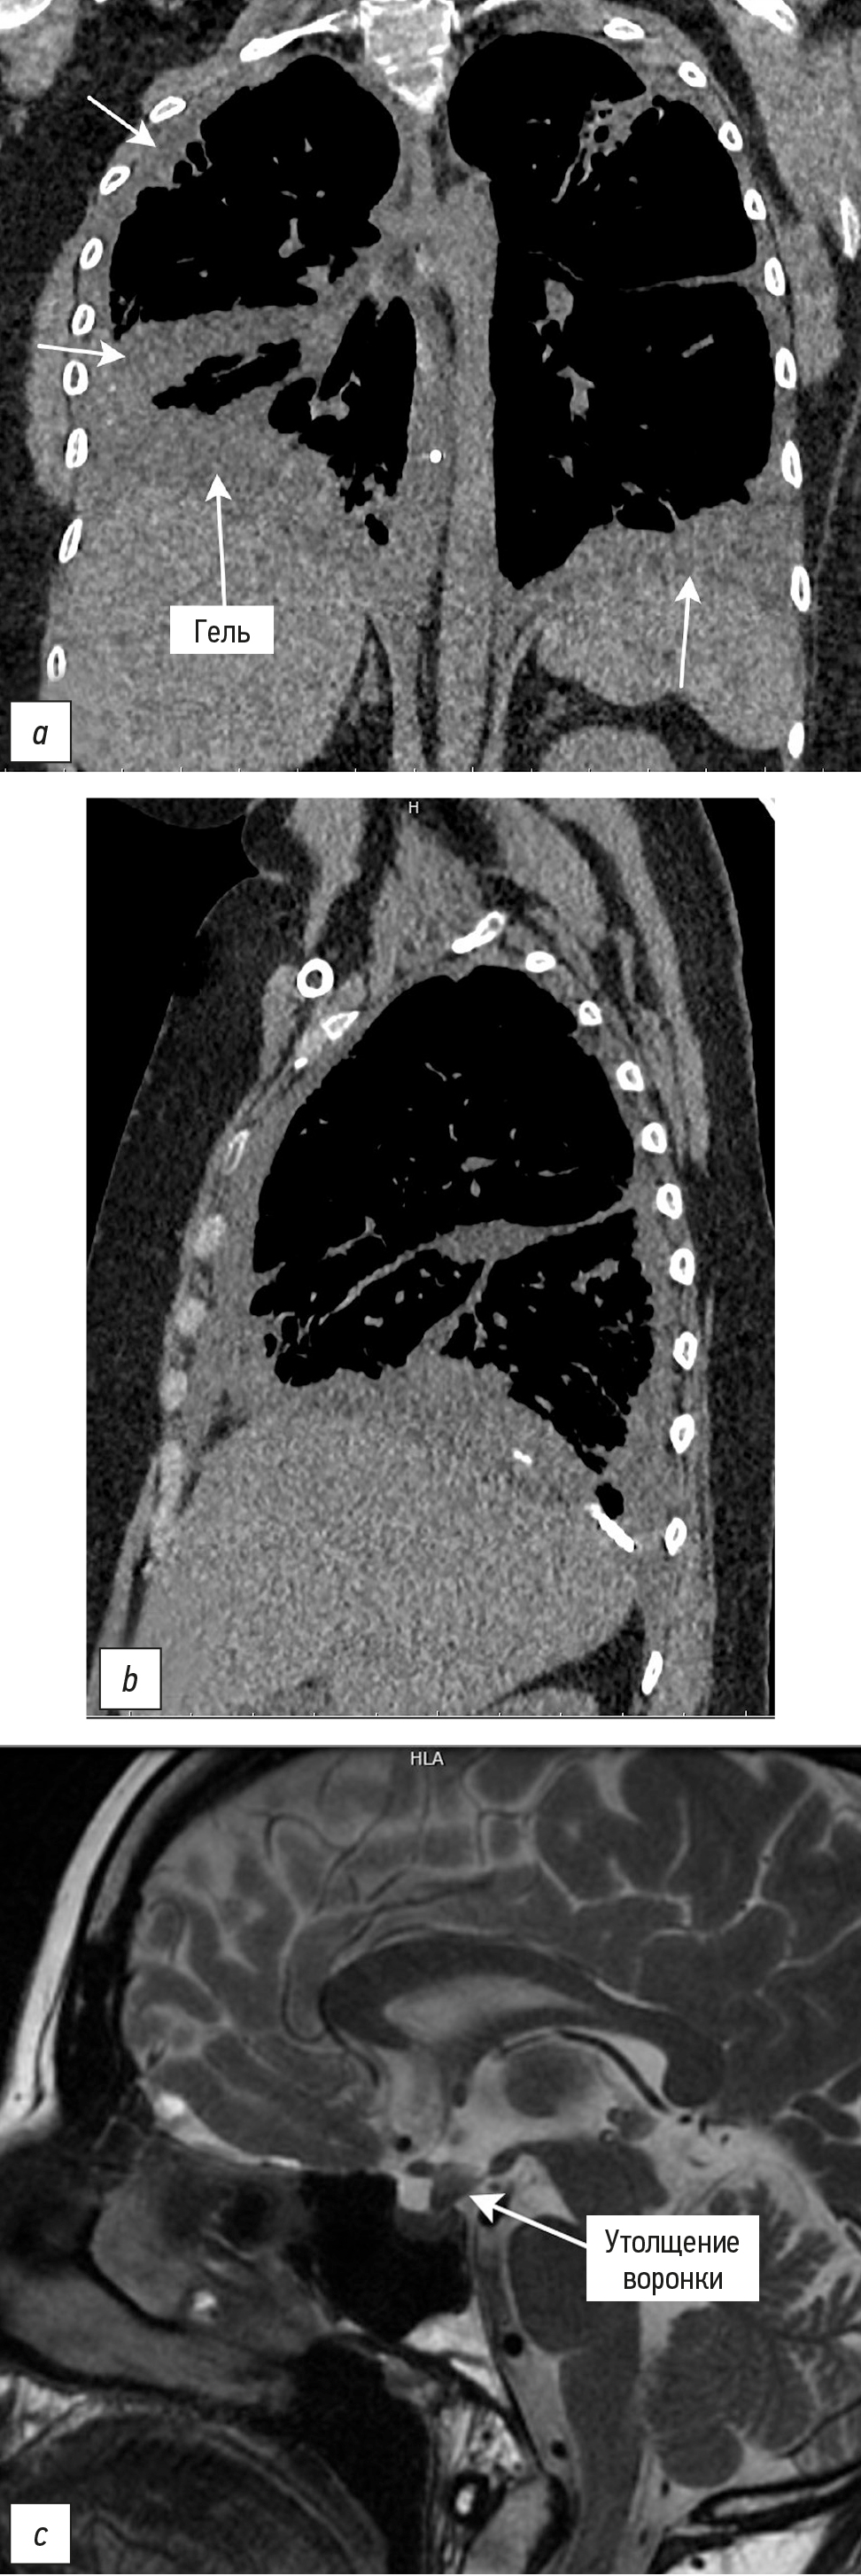

Инструментальная диагностика. Компьютерная томография лёгких (рис. 3): КТ-признаки кистозно-буллёзной трансформации лёгких, пневмофиброза и активного хронического бронхита; состояние после хирургических вмешательств, пневмоторакс отсутствует.

Рис. 3. Инструментальная диагностика: a, b ― компьютерная томография лёгких (КТ-признаки кистозно-буллёзной трансформации лёгких, аппликация силиконовым клеем на месте резекций лёгких); c ― магнитно-резонансная томография головного мозга (утолщение воронки гипофиза, являющееся характерным признаком при гистиоцитозе из клеток Лангерганса). Фото из архива кафедры кожных и венерических болезней им. В.А. Рахманова, зав. Олисова О.Ю., 2025; публикуются впервые.

Fig. 3. Instrumental diagnostics: a, b ― chest computed tomography (CT signs of cystic-bullous lung transformation, silicone glue application at the lung resection sites); c ― magnetic resonance imaging of the brain (pituitary involvement ― thickening of the pituitary stalk, a characteristic feature of Langerhans cell histiocytosis). Photo from the archive of the Department of Dermatology and Venereology named after V.A. Rakhmanov, head O.Yu. Olisova, 2025; published for the first time.

Магнитно-резонансная томография гипофиза с контрастированием (см. рис. 3): утолщение воронки гипофиза, отсутствие сигнала от задней доли, накопление контраста в шишковидной железе; мелкоочаговые изменения в головном мозге, активный очаг в области моста и продолговатого мозга; признаки гистиоцитоза (утолщение мамиллярных тел); двусторонний средний отит; патологический компонент в правой верхнечелюстной пазухе.